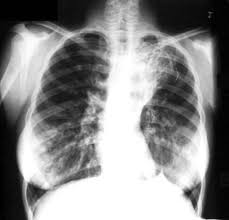

Gambaran Foto Toraks

Pemeriksaan foto toraks standar untuk menilai kelainan pada paru ialah foto toraks PA dan lateral, sedangkan foto top lordotik, oblik, tomogram dan floroskopi dikerjakan atas indikasi. Crofton mengemukakan beberapa karakteristik radiologik pada TB paru:

Rasmin menyatakan bahwa gambaran radiologik TB paru tidak memperlihatkan hanya satu bentuk sarang saja, akan tetapi dapat terlihat berbagai bentuk sarang secara bersamaan sekali gus yang merupakan bentuk khas TB paru. Adapun bentuk sarang yang dijumpai pada kelainan radiologik adalah: sarang dini/sarang minimal, kavitas non sklerotik, kavitas sklerotik, keadaan penyebaran penyakit yang sudah lanjut.

Kelainan radiologik foto toraks hendaklah dinilai secara teliti, karena TB paru dapat memberikan semua bentuk abnormal pada pemeriksaan radiologik dan dikenal dengan istilah "great imitator".

- Bayangan lesi terutama pada lapangan atas paru

- Bayangan berawan atau berbercak

- Terdapat kavitas tunggal atau banyak

- Terdapat kalsifikasi

- Lesi bilateral terutama bila terdapt pada lapangan alas paru

- Bayangan abnormal menetap pada foto toraks ulang setelah beberapa minggu.